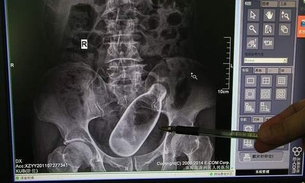

Homem estimulou o ânus com garrafa para ajudar na prisão de ventre